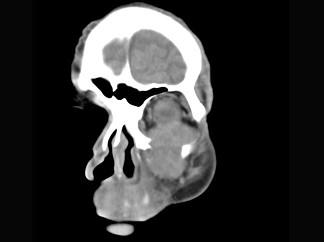

问题 男,65岁,左眼球突出近一年,鼻涕带血,面颊部隆起,同时面颊部有麻木感,CT检查如图,最可能诊断为 ( )

选项 A、上颌窦癌 B、骨肉瘤 C、上颌窦血管瘤 D、上颌窦囊肿 E、上颌窦息肉

答案 A